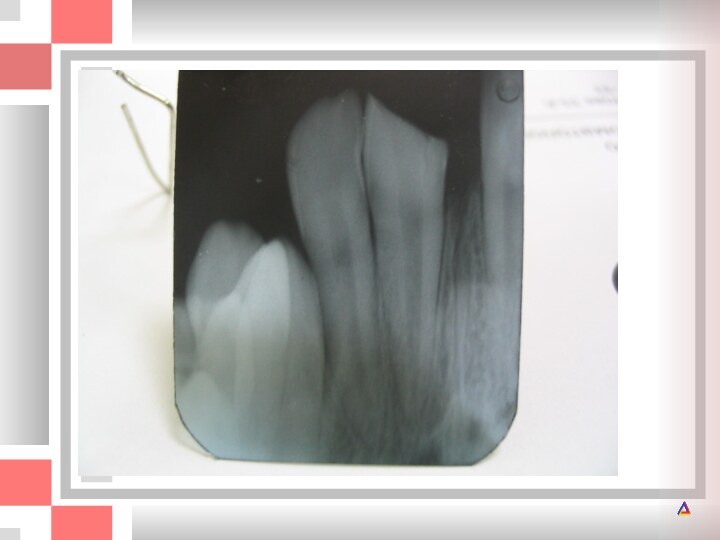

А и Б - перелом коронок верхних центральных резцов с обнажением

резцов с обнажением пульпы. Вся язычная поверхность эмали правого

центрального резца отсутствует. Произведена ампутация пульпы; В - проведена реставрация зубов композитом без препарирования. Дополнительной ретенции удалось достичь за счет заполнения пульпарной камеры пломбировочным материалом. Штифты не использовались.